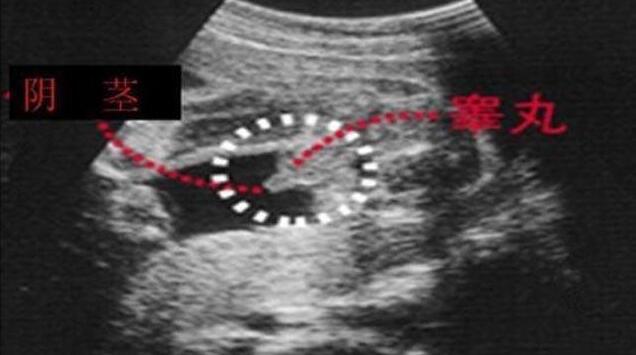

四维彩超男宝宝特征如下

男宝宝如何通过B超分辨出来呢,其实也很简单了,如果角度合适,男宝的B超图上是可以看到小丁丁的。下图拍摄取的角度就是宝宝屁屁正下方,一目了然。

小丁丁